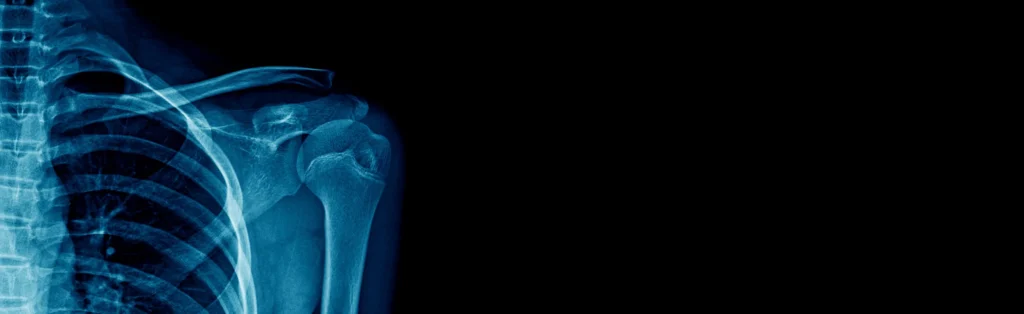

What is a clavicle (collar bone) fracture? A fracture or break in a bone generally occurs secondary to trauma from a fall, commonly during sports...

The acromioclavicular joint is between the collarbone (clavicle) and the acromion, the highest part of the shoulder blade (scapula). Related...